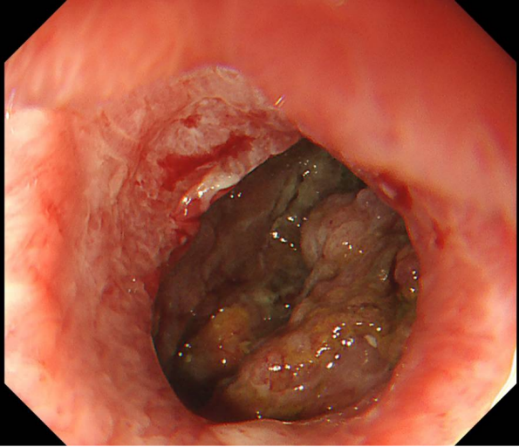

手术当天,超声内镜下,坏死腔清晰呈现。孙家琛成功将穿刺针经胃壁精准置入巨大的坏死包裹腔内,抽出约20毫升褐色坏死液送检。这一步,不仅验证了路径的正确,也为后续抗感染治疗提供了关键的病原学依据。

超声穿刺针精准置入腔内

导丝、切开一气呵成,通道建立。一枚胰腺WON专用引流支架(LAMS)被成功置入,即刻可见大量液体流出至胃腔内。但李阿姨的坏死腔巨大,内容物黏稠。如果只用单支架,一旦堵塞或移位,效果将大打折扣。